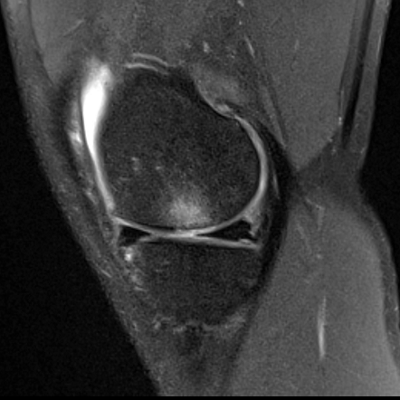

In young active people, an osteochondral lesion (or OCD) of the knee is mostly caused by a traumatic (usually sporting) injury. ‘Clinically, the patient had pain over the medial side of his knee and an MRI revealed an 11x9mm full thickness cartilage lesion,’ Dr Salkinder explains. ‘Articular cartilage does not have its own blood supply and receives its nutrients from the synovial fluid. As a result, it has a very low intrinsic healing potential. In addition to functional impairment which can result in reduced quality of life, osteochondral lesions can lead to the development of osteoarthritis.’